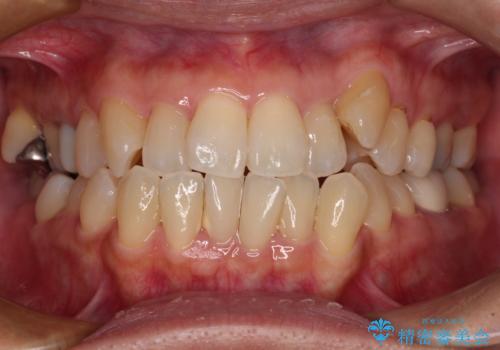

捻れて前に出ている前歯 ワイヤー装置での非抜歯矯正